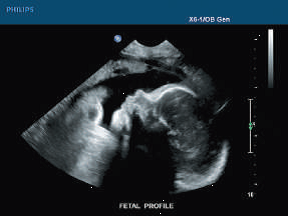

In this regard, US is able to image organ boundaries and internal organ structures, including changes caused by, as an example, tumour growths. The main advantages of US are the real-time nature, capable of live imaging (i.e. video), portability, and (relative) cost.

Figure 4:Cross-section US image of a fetus, image courtesy here, accessed on 2026-02-03.

For US imaging, the resolution scales as the inverse of the acoustic frequency, which for modern equipment is generally less than 1mm (MHz). However, as the acoustic frequency increases, the penetration depth decreases due to the increased absorption, leading to a trade-off between image resolution and penetration depth.

The main application of US is both functional and structural, used to image anatomy with motion (i.e. cardiac with beating heart) or flow (i.e. via Doppler ultrasonography for cardiovascular). US is widely used in cardiovascular, hepatobiliary, pancreatic, renal or gynaecological problems, or in obstetrics to visualise the foetus (Elson & Yang (2010)).